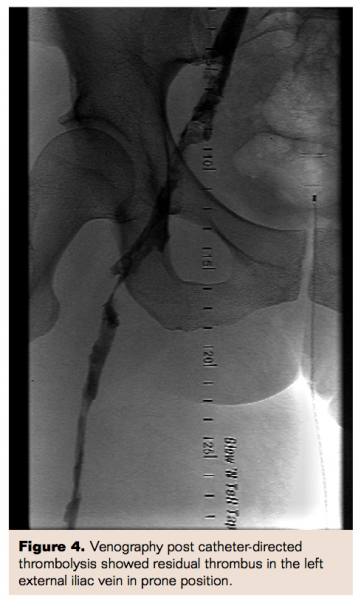

She was then brought back to the catheterization laboratory the next day for venography and her residual thrombus burden was assessed. Venography was performed with demarcation of the limits of residual thrombus and showed some improvement in blood flow. An 8 Fr, 30 cm therapeutic length Trellis device (Covidien Inc) was then advanced with the distal port in the left common iliac vein and proximal port in the left deep femoral vein. Trellis thrombectomy was performed for 10 minutes with a total of 10 mg of tPA administered. Thrombus material was aspirated. The therapy was once again repeated, from the left deep femoral vein to the left popliteal vein. Final images were obtained which showed marked improvement in blood flow. Her left lower extremity swelling along with symptoms of DVT significantly improved within 24 hours and she was discharged home after being started on warfarin oral anticoagulation therapy.